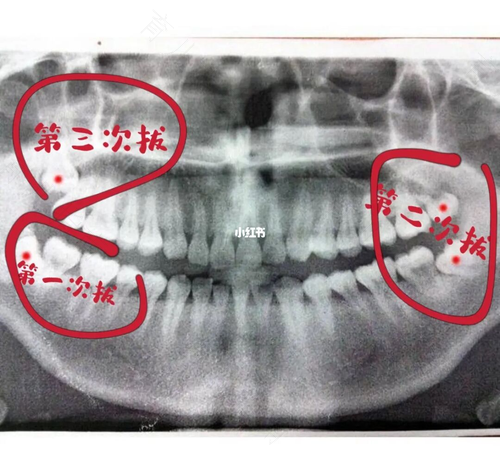

第一,因为下颌智齿的位置比较特殊一些,而且智齿的位置在下颌升支处,位置容易不正,拔起来会比较费劲,拔牙时候的阻力比较大。

第二,拔下面的智齿,每个人的情况都不一样,有些人在拔智齿的时候还需要凿骨,损伤也会比较大一些,操作起来也会更复杂一些,所以在价格方面就会比较贵。